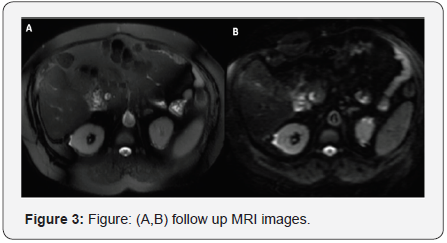

His initial lab data revealed hemoglobin (Hb) of 12.7gm/ dl, total leucocyte count (TLC) of 12.8x103/ccwith 70% neutrophil and 22% lymphocytes and platelet count (PLT) of 1.61lac/cc. electrolyte, blood urea, serum creatinine was normal. Liver function tests (LFTs) showed serum bilirubin (S.Bil)-2.7mg/dl with direct being 0.9mg/dl, AST- 26IU/ ml, ALT-24 IU/ml, serum alkaline phosphatase- 103 IU/ml and /gamaglutamyltranspeptidase of 175 IU/ml, albumin/ globulin(Alb/Glob)-2.9/2.4. Blood and urine cultures were sterile (Figures 1-3).

On suspicion of fever due to biliary complication, a MRI with MRCP was done. It revealed the presence of ill-defined focal and confluent areas of T1 hypointensity /T2-hyperintensity along the portal tracts in graft liver predominantly involving segment-V showing minimal diffusion restriction with biliary radicals coursing through them along with a few diffusion restriction in periportal and peri-pancreatic lymph nodes. Hence raising the suspicion of PTLD. Contrast CT of thorax was non-contributory for the cause of fever. Peripheral smear showed no atypical cells, Bone marrow -normal with LDH-597 IU/ml. Targeted biopsy from the liver showed the normal liver acinar architecture with focal large area of mixed inflammatory infiltrate (A) comprising of dense sheets of plasma cells (orange arrow), lymphoid cells and occasional neutrophils and neovascularization in the background of dense collagenous stroma (B). Portal tract show mild mixed inflammation with periportal spillover with focal lymphocytic duct damage. IHC for EBV was negative but the plasma cells are kappa positive (E) and lambda positive (F), consistent with Polymorphic polyclonal PTLD. EBV DNA was undetectable and the tissue DNA extraction for EBV was also negative. The CMV DNA and HCV RNA were negative. It was again confirmed the EBV IgG was reactive both for donor and recipient in pre LT work up and presently also [3,4].

But being on low dose of immunosuppression, without any history of prior ACR requiring pulsing or increased dose of immunosuppression and post LT 20 months it is difficult to get a conclusion. Tacrolimus and MMF was stopped maintained on prednisolone 20mg and supportive medication. After 2 months on being serial follow up, he became afebrile, LFT normal and repeat MRI reveal-no lesion suggestive of resolution of PTLD.